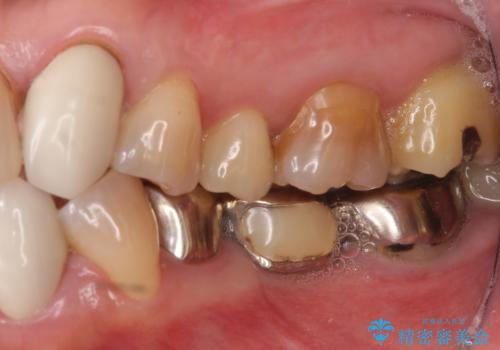

上顎は左側 4 番目から右側 4 番目までの 8 歯をオールセラミッククラウンで補綴しました。

下顎は左側 4 番目から右側 4 番目までの 8 歯と左下 567 ブリッジをオールセラミッククラウンで補綴し、右下67の銀歯はセラミックインレーによる修復を行いました。